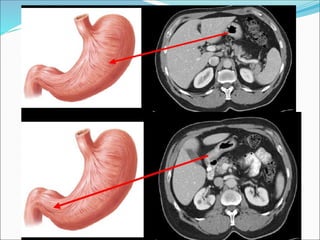

Stomach:

 has a lesser curvature, which is connected to the porta hepatis

of the liver by the lesser omentum, and a greater curvature

from which the greater omentum is suspended.

 The cardiac region receives the esophagus.

 The dome-shaped upper portion of the stomach, which is

normally filled with air, is the fundus.

 The main center portion of the stomach is the body.

 The pyloric portion of the stomach has a thick muscular wall

and a narrow lumen that leads to the duodenum.

3/22/2024 44

3/22/2024 45